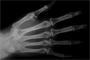

1858: First X-Ray?

Rupert Glitch photographs his own bones